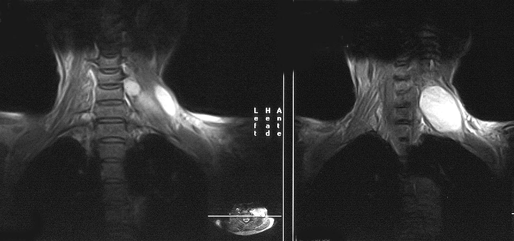

МРТ при шванномах и других новообразованиях в проекции нервного ствола выявляет гиперинтенсивное объемное образование; потерю фасцикулярного рисунка нервов в прилегающей области; участки ствола, граничащие с образованием, имеют гиперинтенсивный сигнал в T2 режиме. Шванномы представляют собой дольковые инкапсулированные округлые или овальные образования, гиперинтенсивные в T2-режиме, изо— или гиперинтенсивные в T1-режиме (рис. 1). Более чем в половине случаев в строме шванном выявляются участки некроза и кистозной дегенерации, они проявляются негомогенными гиперинтенсивными областями в T2-режиме. Нейрофибромы представляют собой неинкапсулированные грибовидные, менее четко отграниченные образования по сравнению со шванномами. Они также гиперинтенсивны в T2-режиме и изо-/гиперинтенсивны в T1-режиме (рис. 2). В отличие от шванном, нейрофибромы обычно не могут быть отделены от материнского нерва, т.к. нервные волокна проходят через опухоль.

Рисунок 2. Нейрофиброма плечевого сплетения (МРТ, Т2-взвешенные изображения)